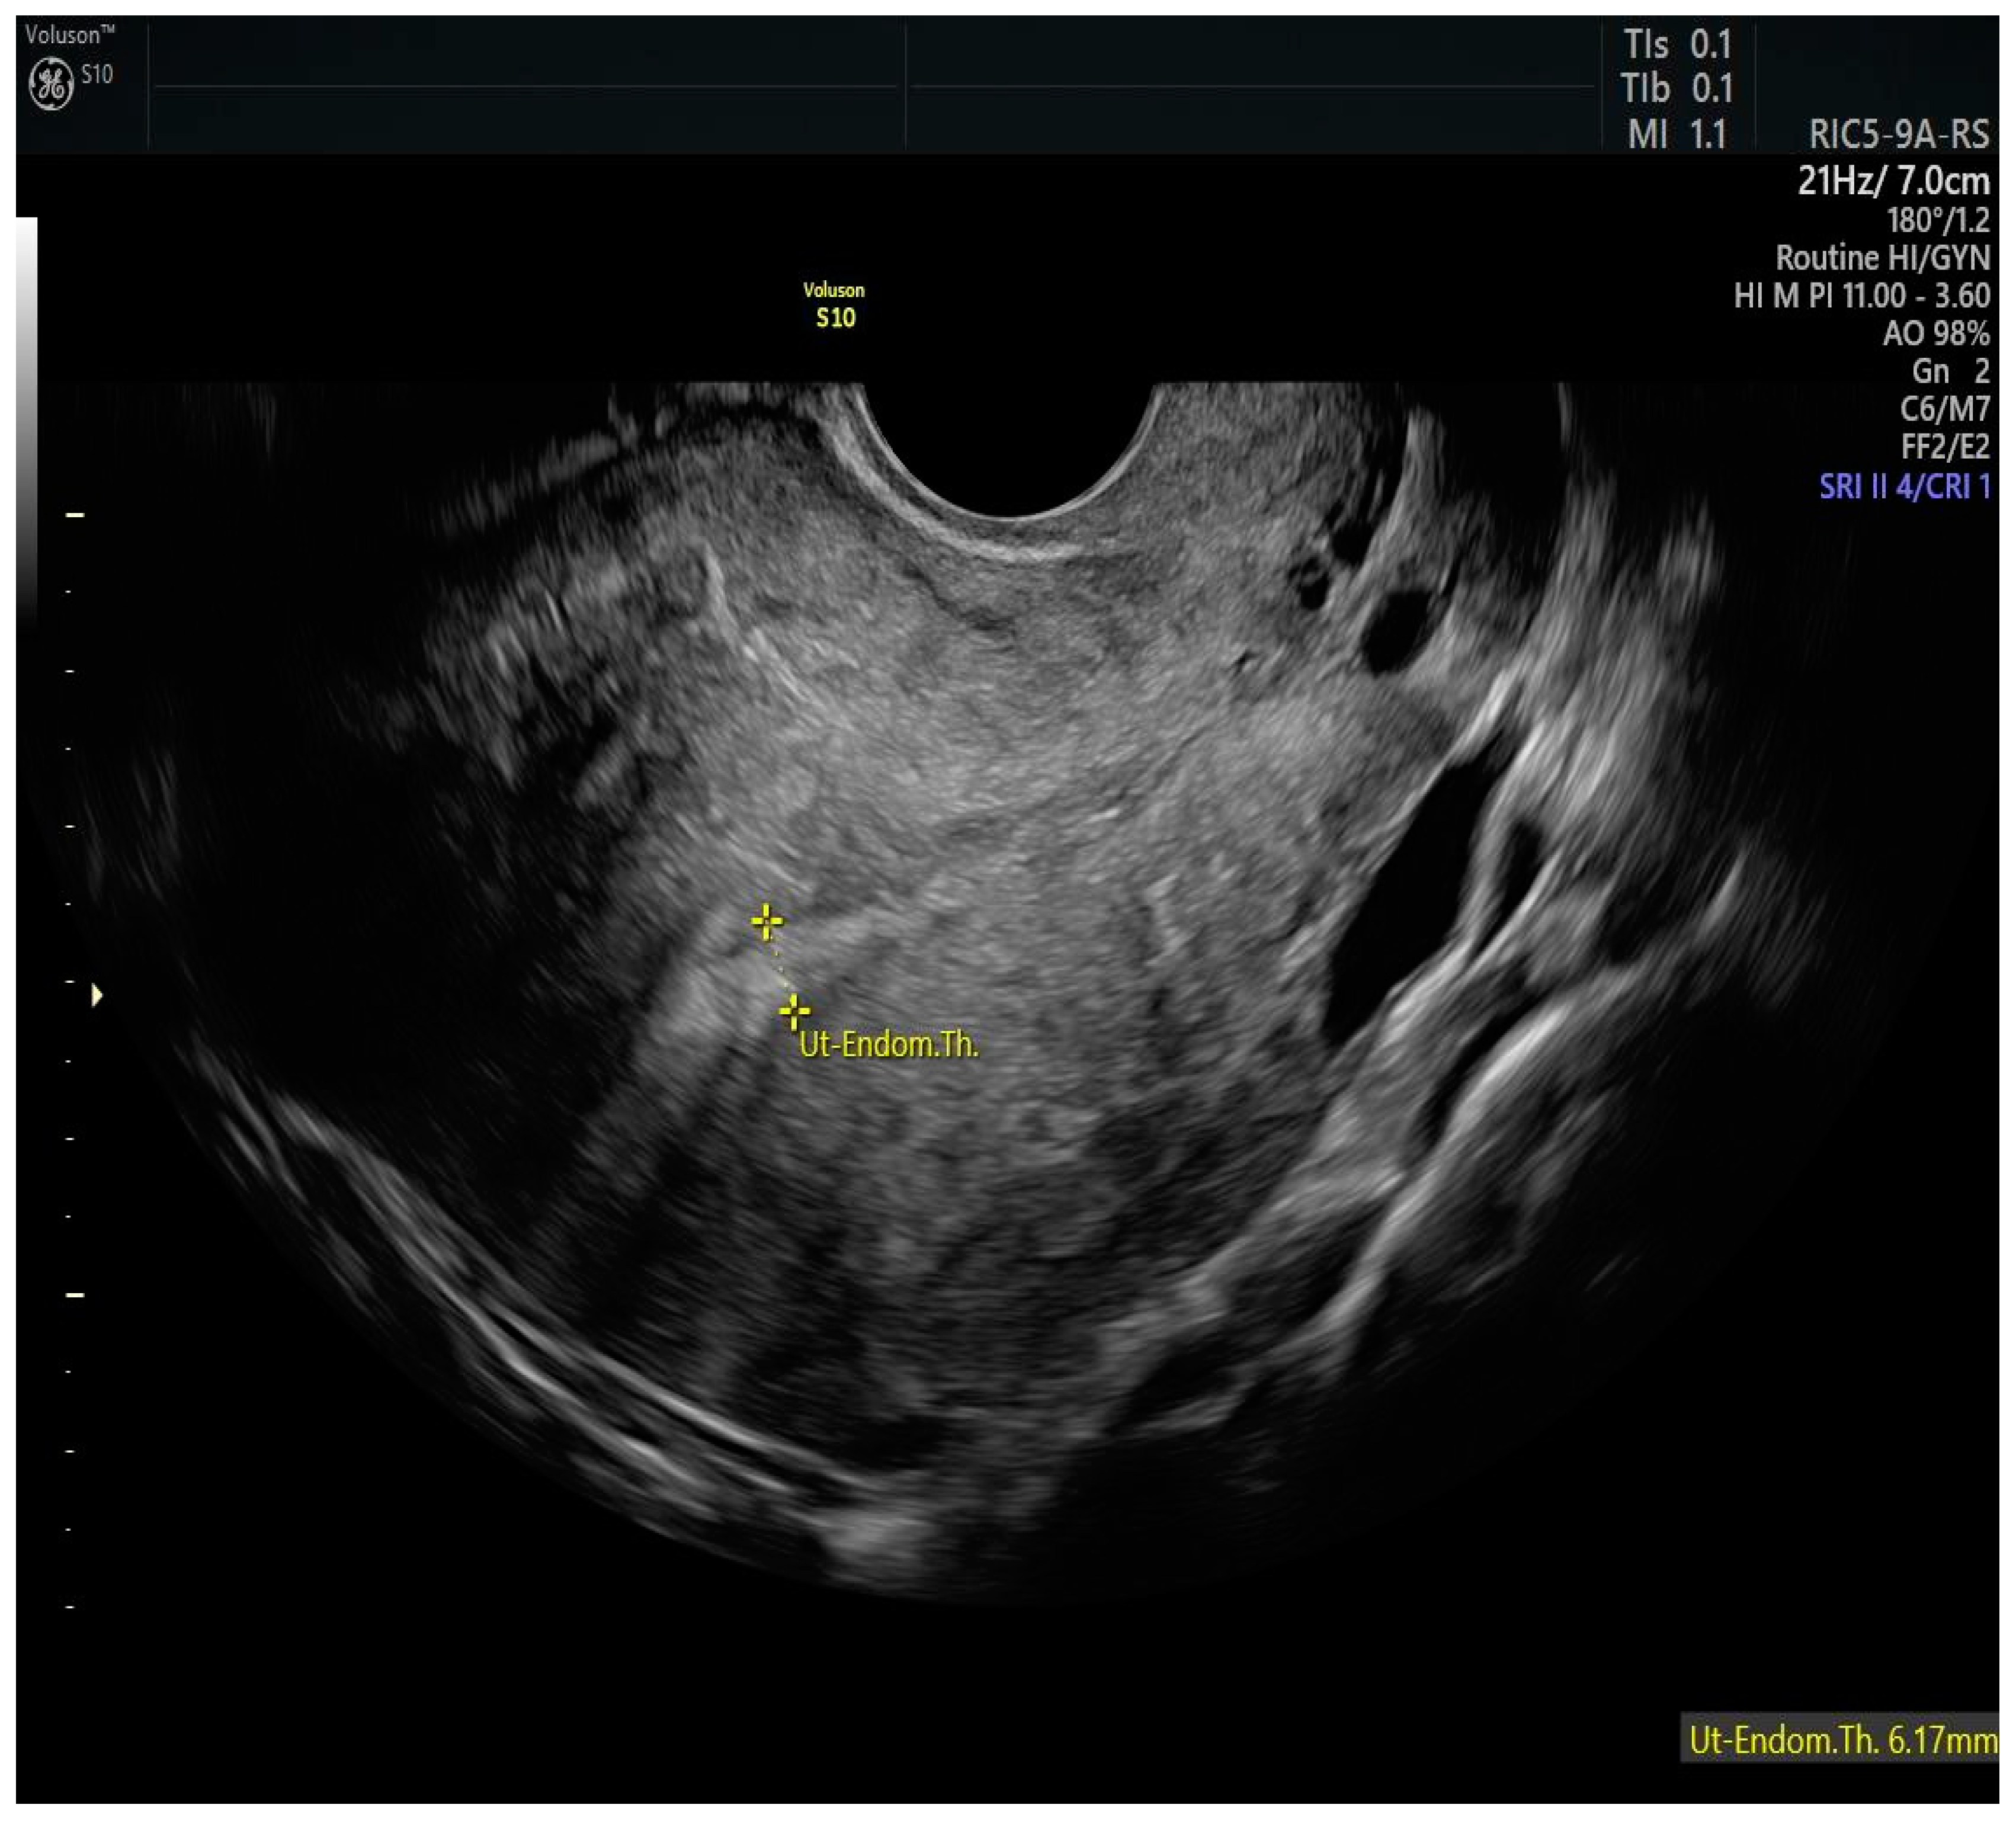

- No evidence of myometrial infiltration;

- No evidence of extrauterine pathology on imaging (TVS/RM/CT);

- Epstein, E.; Fischerova, D.; Valentin, L.; Testa, A.C.; Franchi, D.; Sladkevicius, P.; Frühauf, F.; Lindqvist, P.G.; Mascilini, F.; Fruscio, R.; et al. Ultrasound characteristics of endometrial cancer as defined by International Endometrial Tumor Analysis (IETA) consensus nomenclature: Prospective multicenter study. Ultrasound Obstet. Gynecol. 2018, 51, 818–828. [Google Scholar] [CrossRef]